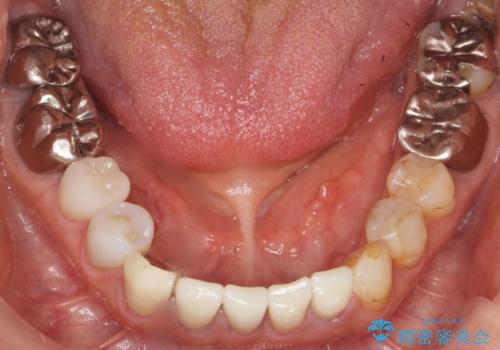

根管治療後、セラミッククラウンによる補綴治療を行いました。

根管治療により痛みがなくなり、ご安心頂けました。

セラミッククラウンの自然な仕上がりにも喜んで下さいました。

クラウンの種類:オールセラミッククラウン エコノミー